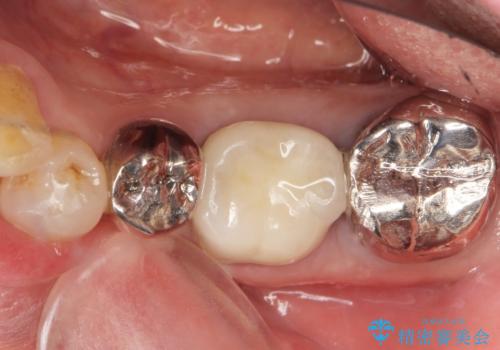

保存不可能な奥歯(左下6)を抜歯し、機能していない親知らず(左下8)の移植を行いました。

移植後、生着を待って根管治療及び補綴修復を行いました。

被せ物の種類:メタルボンドクラウン エコノミー